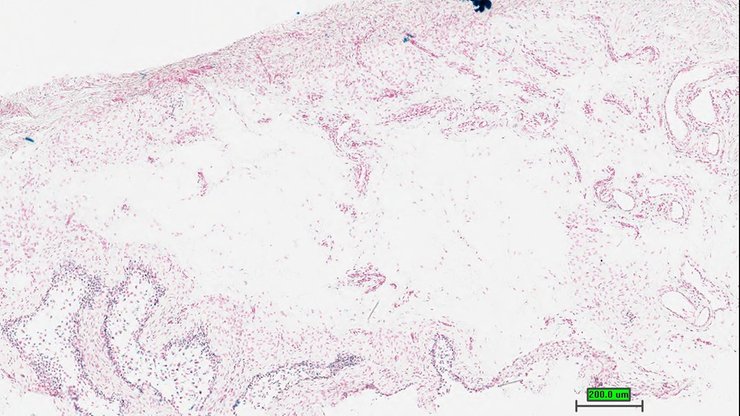

TS28: skin Present UC Davis_1865756

Specimen UC Davis_1865757: postnatal adult; Angtm1.1(KOMP)Vlcg/Ang+ (more )

Structure Level Pattern Image Note

TS28: skin Present UC Davis_1865757

TS28: skin Present UC Davis_1865794

Specimen UC Davis_1865795: postnatal adult; Angtm1.1(KOMP)Vlcg/Ang+ (more )

TS28: skin Present UC Davis_1865795